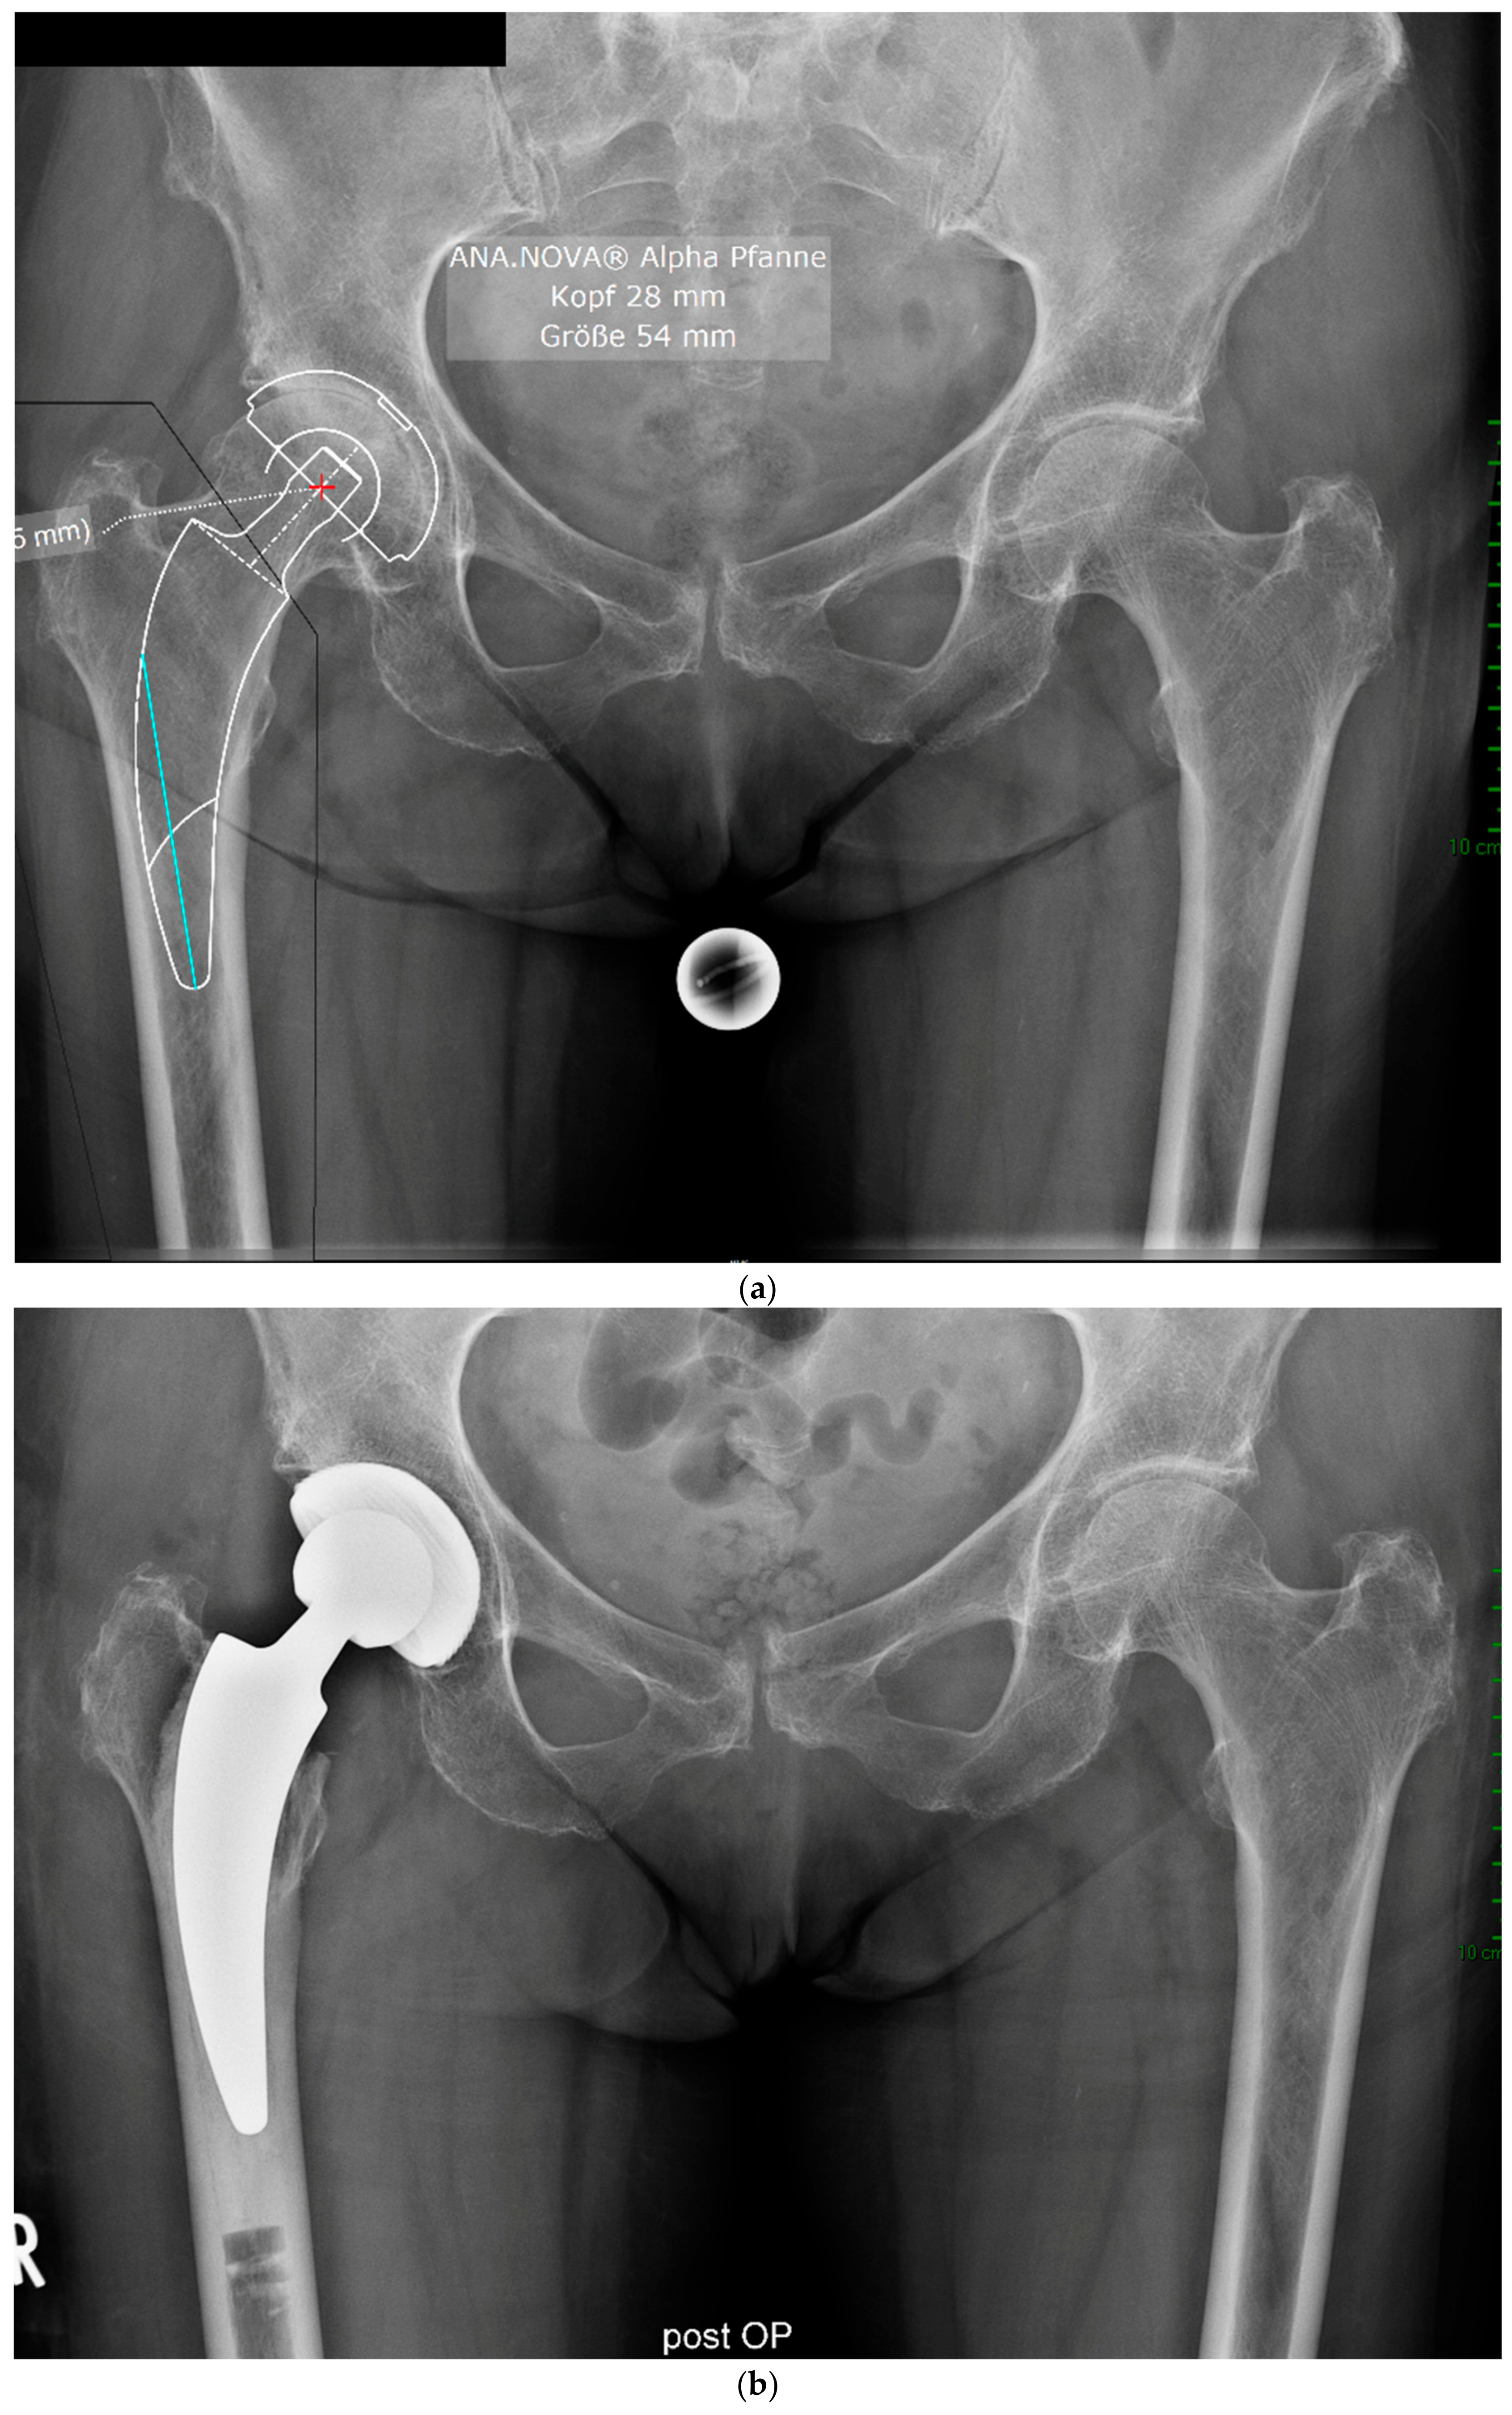

The mean HHS increased from 49.4 ± 13.9 preoperatively to 93.6 ± 6.9 at the final follow-up. No pain was reported by 19 patients at the final follow-up, with only occasional slight pain in one patient. The mean UCLA score increased from 3.5 ± 1.5 preoperatively to 5.1 ± 1.9 at the one-year follow-up. The mean HOOS-PS score increased from 44.2 ± 22.1 preoperatively to 60.0 ± 28.6 at the one-year follow-up. The FJS score was 68.3 ± 14.6 at the one-year follow-up. One patient experienced leg shortening of 10 mm. Periarticular ossification Brooker 1 was identified in three patients. One patient experienced axial subsidence of 2 mm. There were no postoperative infections. No radiolucent lines were observed, and none of the patients presented with osteolysis. A representative case is presented. Preoperative planning facilitated the achievement of anatomic restoration, as depicted in Figure 2. Figure 3 and Figure 4 demonstrate the correct postoperative positioning of the femoral stem and a complete cement mantle.

Figure 2.

Case #1: Female patient, 81 years old, with osteoporotic bone, coxa vara, and a Dorr C femur. (a) Preoperative planning for a cemented A2 stem combined with a cementless ANA.NOVA Alpha Cup. The image shows good reconstruction of the leg length and offset. (b,c) Postoperative anteroposterior (b) and axial (c) radiographic imaging 1 week postoperatively. Correct position of the stem and complete cement mantle.